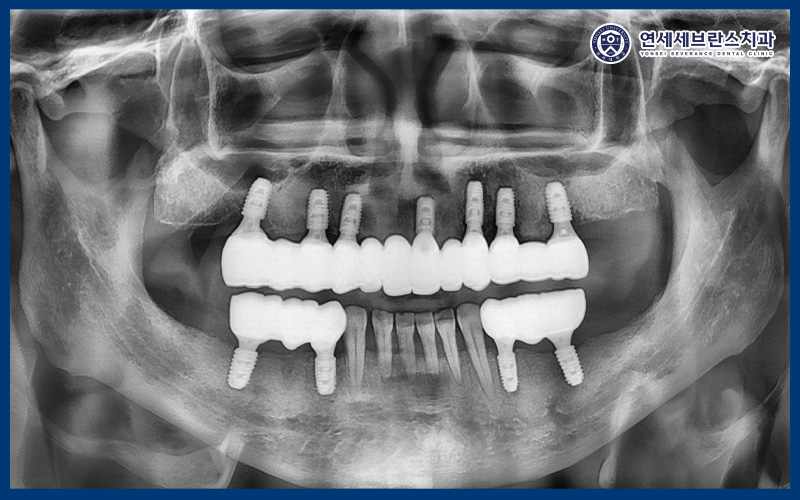

26.01.12

치료 마무리 후 파노라마 사진을

찍어보았을 때도

임플란트가 계획한 위치에

안정적으로 식립된 모습을 확인할 수 있었으며,

전체적인 배열과 교합 균형 역시

양호한 상태로 유지되고 있었습니다.